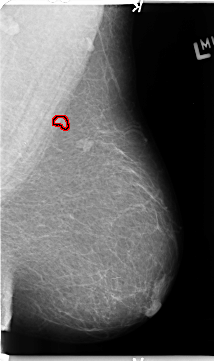

ics_version 1.0 filename B-3153-1 DATE_OF_STUDY 13 5 1998 PATIENT_AGE 69 FILM FILM_TYPE REGULAR DENSITY 1 DATE_DIGITIZED 21 4 1998 DIGITIZER LUMISYS LASER SEQUENCE LEFT_CC LINES 4688 PIXELS_PER_LINE 2720 BITS_PER_PIXEL 12 RESOLUTION 50 OVERLAY LEFT_MLO LINES 4688 PIXELS_PER_LINE 2776 BITS_PER_PIXEL 12 RESOLUTION 50 OVERLAY RIGHT_CC LINES 4728 PIXELS_PER_LINE 2760 BITS_PER_PIXEL 12 RESOLUTION 50 NON_OVERLAY RIGHT_MLO LINES 4736 PIXELS_PER_LINE 2872 BITS_PER_PIXEL 12 RESOLUTION 50 NON_OVERLAY |

FILE: B_3153_1.LEFT_MLO.OVERLAY TOTAL_ABNORMALITIES 1 ABNORMALITY 1 LESION_TYPE MASS SHAPE IRREGULAR MARGINS ILL_DEFINED-SPICULATED ASSESSMENT 4 SUBTLETY 3 PATHOLOGY BENIGN TOTAL_OUTLINES 1 BOUNDARY |